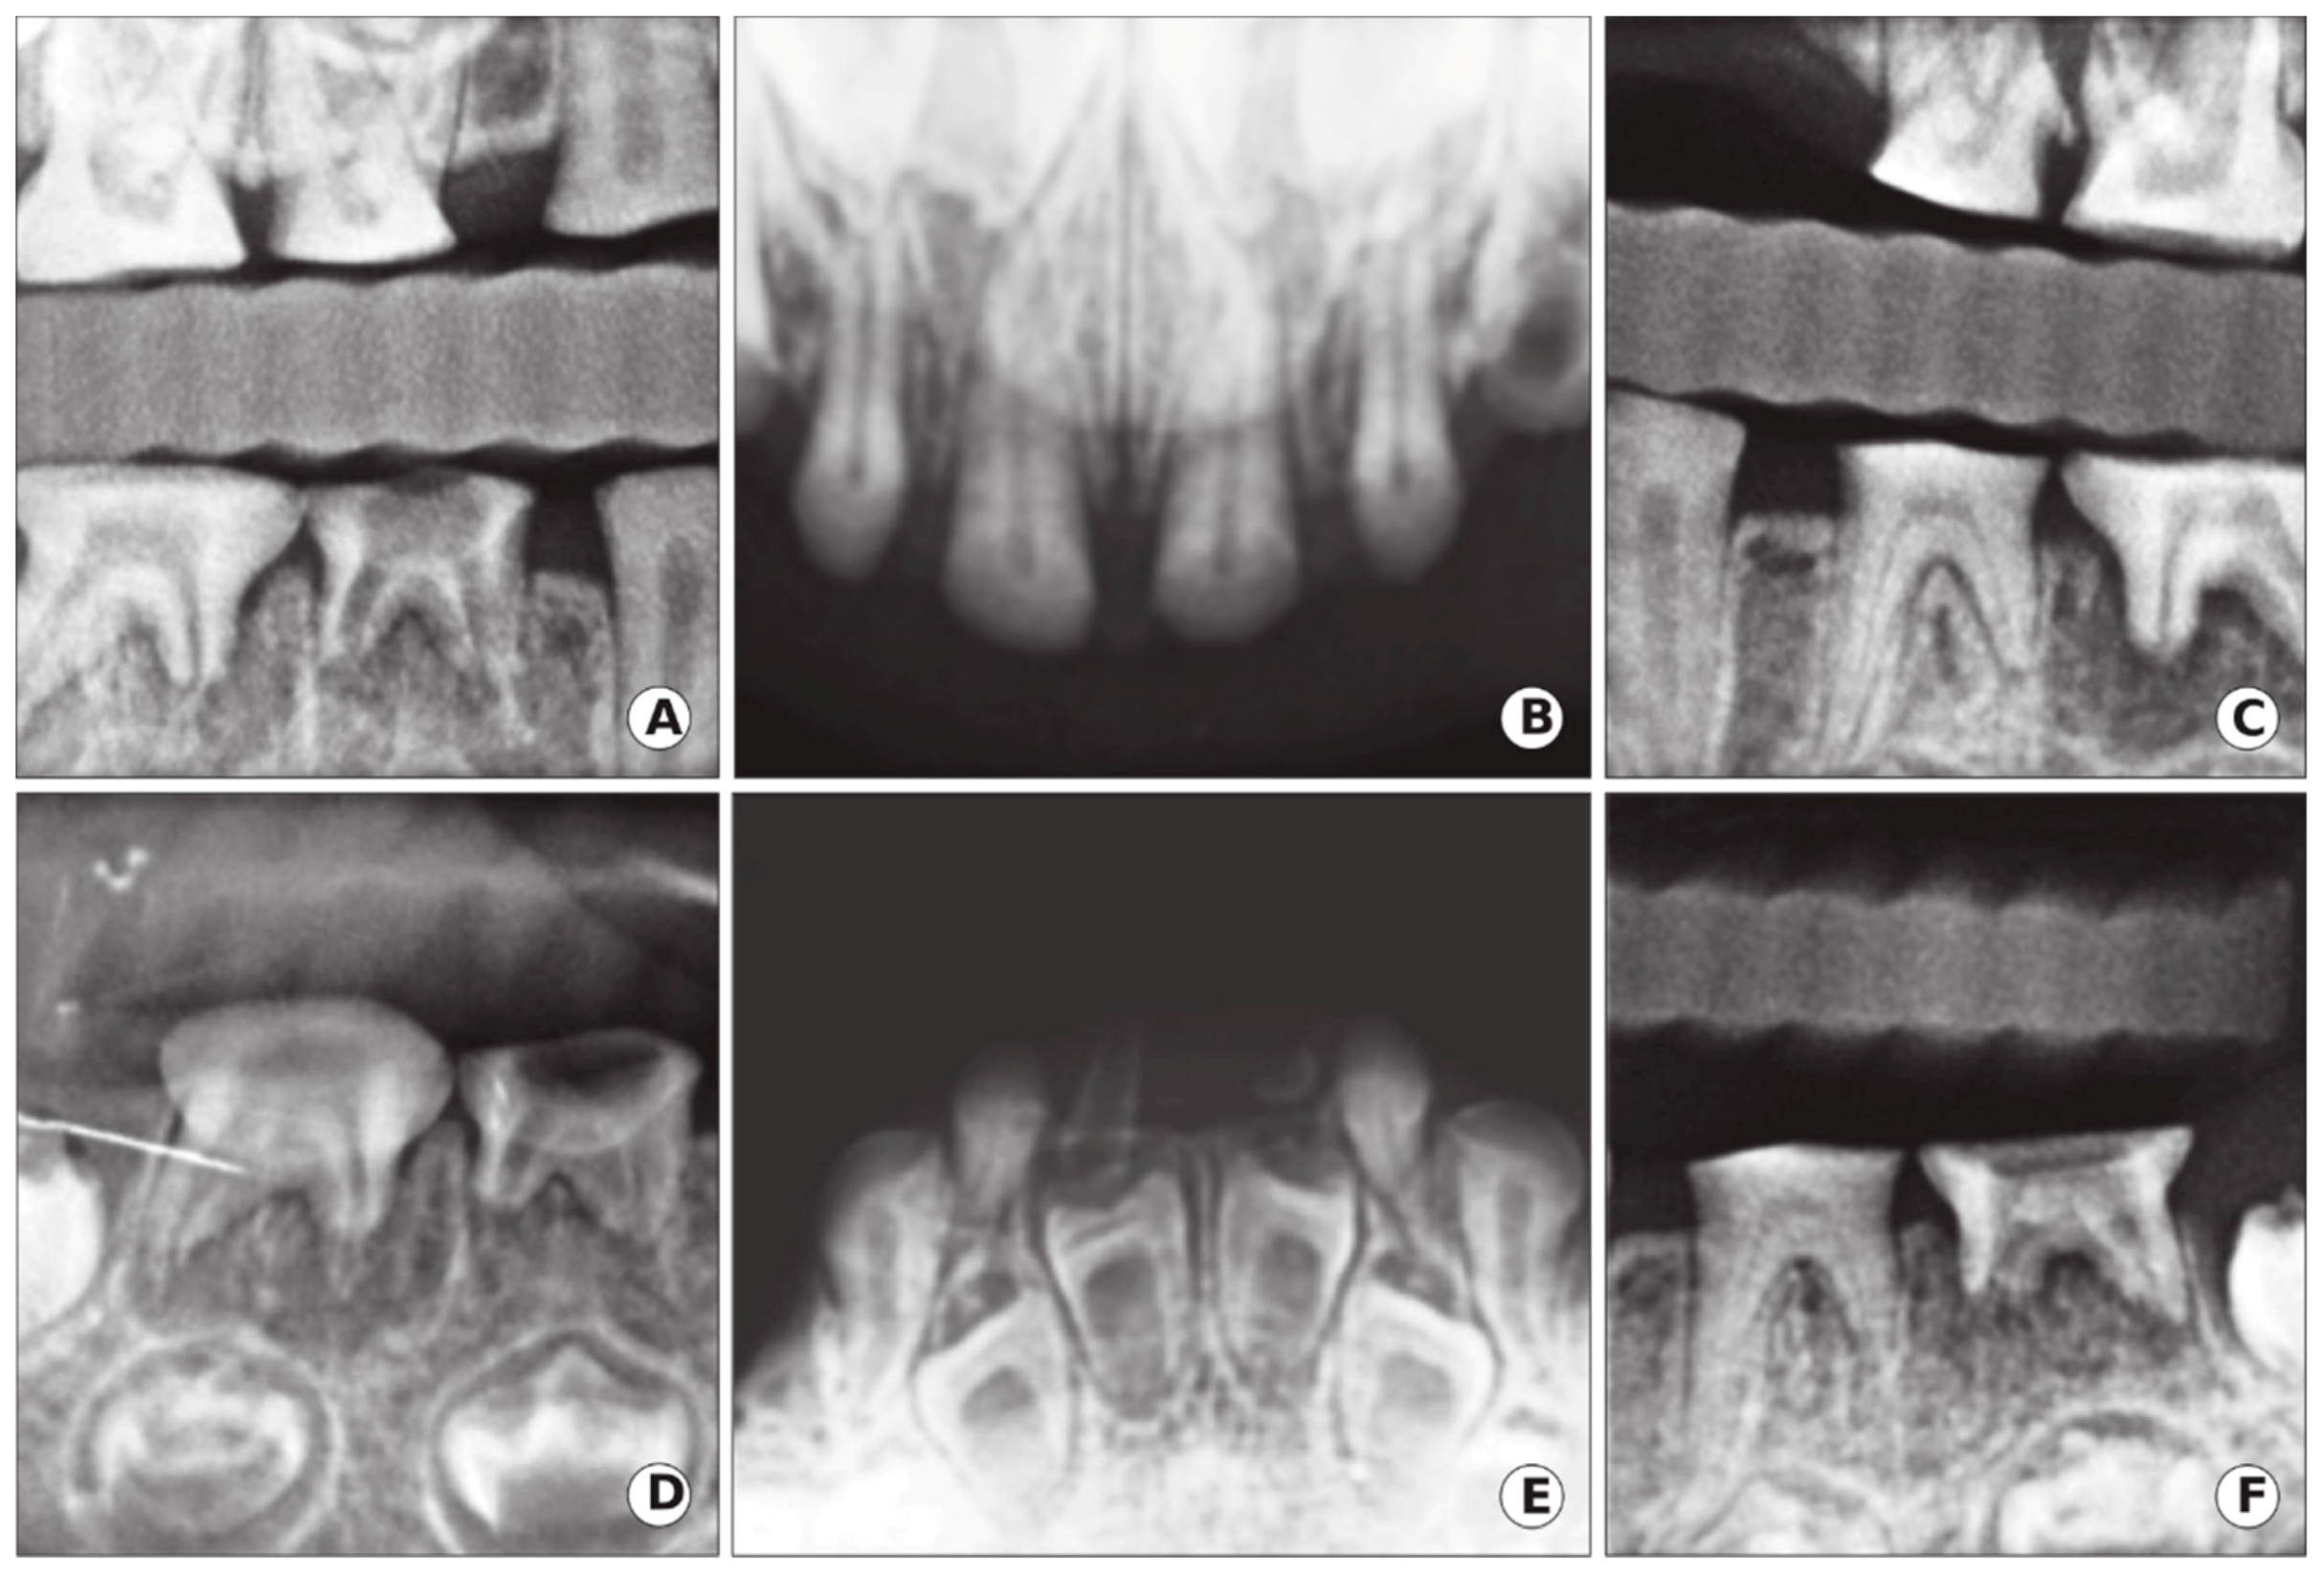

Radiographic examinations revealed a primary dentition present with severe loss of the enamel associated with severe occlusal attrition. Primary upper and lower left second molars, and primary right first and second molars had pulpal involvement with a periapical radiolucency. The presence of developing permanent buds was also evident with thin enamel, large pulp chambers, and mild cervical constriction of the crowns. The child’s dental age, determined radiographically, was consistent with her chronological age (Figure 4).

Figure 4.

Case 1: Radiographic oral manifestation of DGI-II in the proband of the 5-year-old girl of the DGI-II family. (A,C) Bitewings radiographs showed that dentine was thin with severe occlusal attrition. (B,E) Upper and lower occlusal radiographs showed incisal attrition with narrowing of the pulp, in addition to enlarge pulp chambers and thin enamel in the developing lower anterior permanent teeth. (D,F) Periapical radiographs of the lower right and left molars demonstrated occlusal attrition and abscessed second right and left molars.